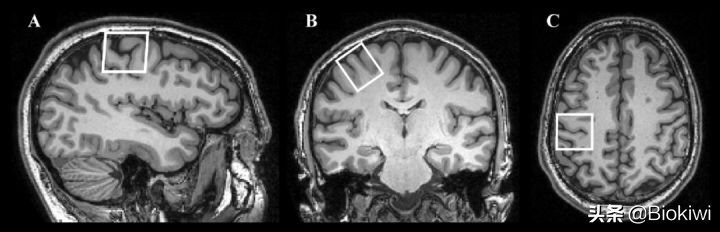

而神经学家则利用现代更清晰的大脑成像,对左撇子和右撇子进行了统计,看他们的左右大脑差异。

他们也找到了很有意思的结果:左撇子的左右脑差异相较于右撇子的更小,并且男性的这种差异更明显。

左右脑在成像上一些显著的差异(图源:Yousry et al.)